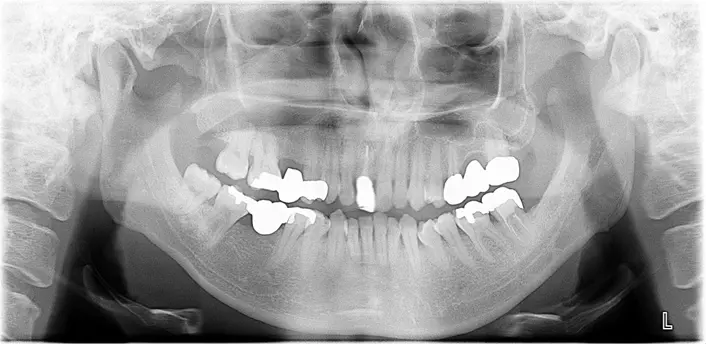

case15

症例15

| 治療ケース | 骨造成(サイナスリフト、GBR)、インプラント埋入、オールセラミッククラウン、セラミックインレー、ハイブリッドセラミック充填(ダイレクトボンディング)、ファイバーコア、ホワイトニング |

| 症状 | 右上が痛い |

| 治療結果 | 右上が痛い、ブリッジの所を治療したいとの事で来院されました。骨造成(サイナスリフト、GBR)を行い待機期間を経て1次手術、2次手術を行いプロビジョナルを装着後問題の無いことを確認して最終上部構造を装着。歯が入った後経過も良く、安定している状態です。 |

| 治療開始月 | 2024年7月 |

| 治療期間 | 約14ヶ月 |